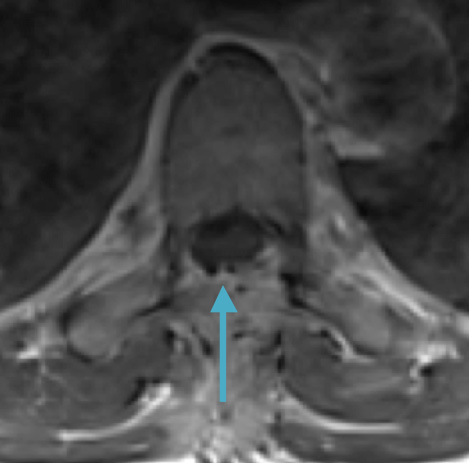

Postoperative MRI T1w demonstrating interval resection with cord re-expansion (blue arrow)

Postoperative MRI T2 illustrating the restoration of CSF surrounding the cord (blue arrow)

Postoperative MRI T1w demonstrating a gross total resection